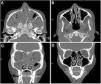

Mujer de 34 años con antecedente de pansinusitis y asma de difícil control. Desde el año 2006 (21 años de edad) presentó crisis frecuentes de broncoespasmos y consultas al servicio de urgencias, 2 internaciones en terapia intensiva. En el año 2011 fue internada por dolor abdominal agudo, en el laboratorio se evidenció eosinofilia periférica (518cél/mm3), elevación de IgE y p-ANCA MPO positivo. Se realizó biopsia endoscópica donde se observó gastroduodenitis eosinofílica. Se diagnosticó GEPA, y se inició tratamiento con meprednisona y azatioprina, el cual fue suspendido por osteonecrosis de ambas rodillas y leucopenia severa. Posteriormente fue tratada secuencialmente con ciclofosfamida, omalizumab y rituximab. Evolucionó con mal control del asma, pansinusitis persistente, vasculitis recurrente en piel, pérdida de peso y ascenso de eosinófilos (1.224cél/mm3). En agosto de 2016 inició tratamiento con mepolizumab 100mg/mes, con franca mejoría clínica, radiológica (fig. 1) y descenso de eosinófilos a 46cél/mm3, las cuales se sostienen hasta el momento.

Tomografía de senos paranasales, corte axial (A y B) y corte coronal (C y D). A y C) Pre-tratamiento con mepolizumab: desviación septal a izquierda. Marcado engrosamiento mucoso de ambos senos maxilares, celdillas etmoidales y ambas fosas nasales. Presencia de exudado a nivel de ambos senos maxilares. B y D) Después de 4 meses de tratamiento con mepolizumab: mínimo engrosamiento de los senos maxilares. Engrosamiento mucoso y formaciones polipoideas de ambas fosas nasales.